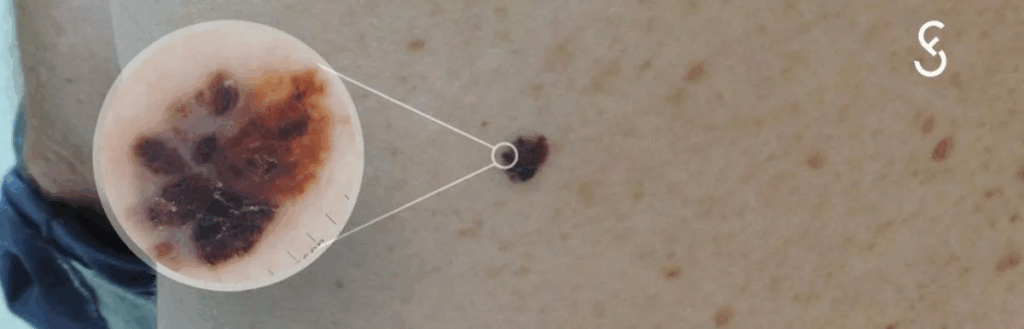

CÂNCER DE PELE: CIÊNCIA, CUIDADO E REFLEXÃO

Um convite ao cuidado que une ciência, consciência e fé. Ao longo dos anos de consultório, sempre que olho a pele de alguém eu me lembro: ela é o nosso maior órgão, nosso “envoltório de vida”, um presente de Deus que nos protege, sente, comunica e guarda histórias. Cuidar dela não é vaidade — […]